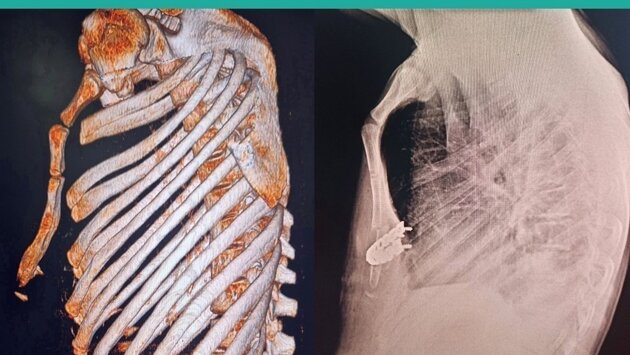

Врачи Центра травматологии исправили килевидную деформацию грудной клетки 14-летнему подростку. Это аномалия, при которой передняя часть грудной клетки выступает, приобретая форму лодочного киля. Консервативное лечение в таких случаях малоэффективно, требуется хирургическое вмешательство.

Металлостернохондропластику с остеотомией грудины проводил главный врач Центра Михаил Яговкин.

Мы отделили кожу, подкожную клетчатку и грудные мышцы от грудины и рёбер, отсекли от грудины прямые мышцы живота и мечевидный отросток. Провели резекцию реберных хрящей с сохранением надхрящницы. На грудину и концы 6-х ребер с обеих сторон уложена отмоделированная титановая пластина, зафиксирована специальными винтами. Операция длилась 2,5 часа, деформация грудной клетки полностью скорректирована, – рассказал Михаил Яговкин.